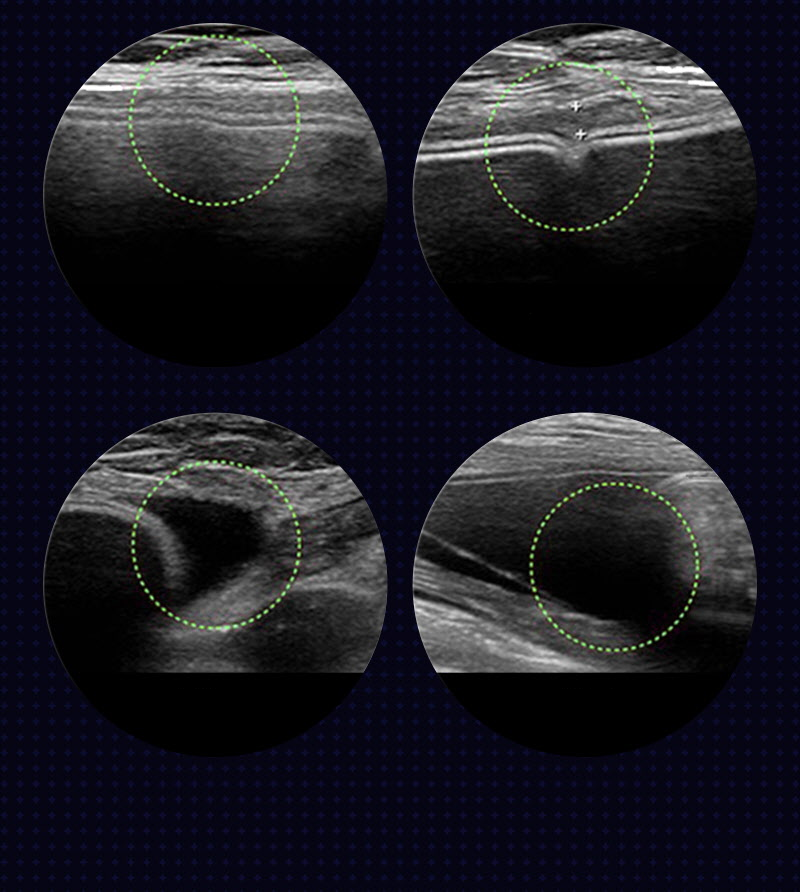

We establish a surgical plan after checking the position of the implant, rupture, capsular contracture, capsule thickness, and cause of edema through ultrasound examination.

We perform revision surgery to improve issues such as capsular contracture, breast asymmetry, implant rupture, dissatisfaction with shape, and rippling.